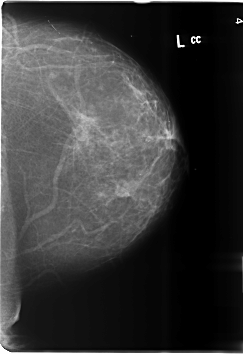

ics_version 1.0 filename B-3486-1 DATE_OF_STUDY 1 6 1998 PATIENT_AGE 39 FILM FILM_TYPE REGULAR DENSITY 1 DATE_DIGITIZED 4 6 1999 DIGITIZER LUMISYS LASER SEQUENCE LEFT_CC LINES 6016 PIXELS_PER_LINE 4128 BITS_PER_PIXEL 12 RESOLUTION 50 NON_OVERLAY LEFT_MLO LINES 6000 PIXELS_PER_LINE 4184 BITS_PER_PIXEL 12 RESOLUTION 50 NON_OVERLAY RIGHT_CC LINES 6024 PIXELS_PER_LINE 4144 BITS_PER_PIXEL 12 RESOLUTION 50 OVERLAY RIGHT_MLO LINES 6024 PIXELS_PER_LINE 4120 BITS_PER_PIXEL 12 RESOLUTION 50 OVERLAY |